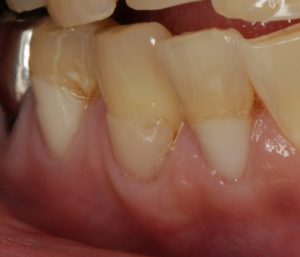

今日は、よくある症例をお見せします。歯の根元が、茶色くなってしまっている方いらっしゃいませんか?これは、歯肉がやせて歯の根が露出した後に起こる症状です。歯の根の虫歯ですね。

しかし、これをきれいに治すのが意外と難しいんです。特に、歯肉との境目をきれいに仕上げるのは至難の業です。この症例は、治したところの色と形態がマッチしていなかったためやり直しをしたものです。